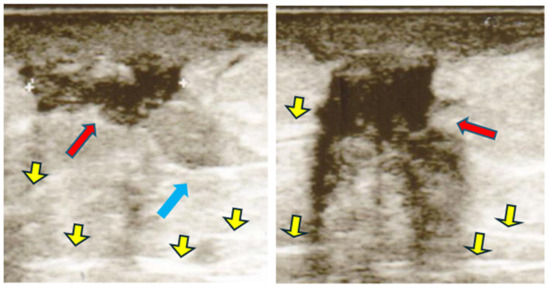

- Hyper type A: iso-hyperechogenic with predominantly fibrotic component.

- Isotype B: isoechoic associated with small edematous islands delimited by fibrous stripes.

- Iso-hypo type C: iso-hypoechoic without fibers.

Ultrasonographic characteristics of LH

| 15.3% 29.2% 65.0% | 14.8% 20.2% 55.5% | 47.3% 22.4% 30.3% |